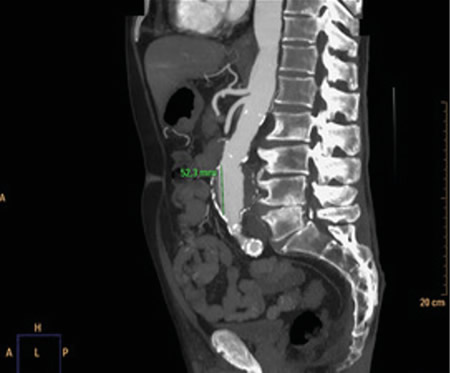

Respecto a las pruebas complementarias, en la analítica sanguínea, se halla una PCR de 39,1 mg/l, leucocitosis de 21.300/mm3, con 88 % de neutrófilos, y una hemoglobina de 10,5 g/dl. En la radiografía pélvica no se evidencian hallazgos patológicos. Debido a la hipotensión, se decide realizar un TC abdominal (Figuras 1 y 2), en el que se objetiva un aneurisma de aorta infrarrenal roto, con diámetro de 50 x 52 x 48 milímetros, a 50 mm de arteria renal derecha y a 65 mm de arteria renal izquierda, craneal a la bifurcación ilíaca. Asimismo, se aprecia un hematoma retroperitoneal en contexto de sangrado en parte posterior de la aorta, que infiltra el músculo psoas ilíaco izquierdo, justificando la clínica de coxalgia con irradiación izquierda. Se contacta con cirugía vascular, interviniéndose de forma urgente, con buena evolución posterior.

Fig. 1. TC coronal de aneurisma de aorta abdominal.